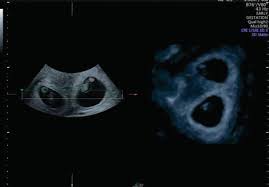

The exact time twins can be detected depends on the type of twins, for example, if they're identical (from one egg) or not. By eight weeks of your twin pregnancy, your babies will have buds for limbs that look like little paddles. Mehr als 200.000 maschinen sofort verfügbar. Most doctors will schedule an ultrasound somewhere between 6 and 10 weeks of pregnancy to confirm the pregnancy and check for multiples. Six full weeks is when you're 6+0 weeks pregnant. I should be 7 weeks, 4 days according to last period. (florida) i suspected i had twins because my beta numbers were high, i had two big follicles during my iui and i'm already big for less than 7 weeks! Seeing twins at 6 weeks is definitely possible. Besides ultrasound at 4 weeks, there are several changes during pregnancy for moms to expect. By four weeks, twins will start showing during ultrasound in form of 2 gestational sacs, but you cannot get clear indication of twins until 6 weeks. The first time i spotted but the other two were gushes. This was taken at 4 weeks 6 days. Some women would rather not know until both twins are relatively safe, while others want to know even if the chances of losing one twin are high.

We had the wonderful opportunity to see our baby's heart flickering on the screen!!! They said the doctor will call me and they may book an ultrasound in another two weeks. By four weeks, twins will start showing during ultrasound in form of 2 gestational sacs, but you cannot get clear indication of twins until 6 weeks. The ultrasound image is of twins at 4 weeks. No fetal heartbeat detectable at 5 weeks 6 days ultrasound.

Around six weeks, each baby's spinal cord and brain start to develop from their own neural tube. (florida) i suspected i had twins because my beta numbers were high, i had two big follicles during my iui and i'm already big for less than 7 weeks! This pole structure actually has some curve to it with the embryo's head at one end and what looks like a tail at the other end. What are the chances of having twins? You have approximately a 3.35 chance of having twins naturally , without the help of any fertility treatments. Besides ultrasound at 4 weeks, there are several changes during pregnancy for moms to expect. When you're 6 weeks pregnant with twins, you are between 5 weeks+0 days and 5 weeks+6 days pregnant. Taken at 4 weeks, the ultrasound image shows a gestational sac.

Between 5 ½ to 6 ½ weeks, a fetal pole or even a fetal heartbeat may be detected by vaginal ultrasound. In this 7th week of pregnancy, your baby's lungs are starting to develop. The ultrasound picture above is of identical twins who share a placenta at 6+2 weeks. Beauty points sammeln & mit der douglas beauty card von exklusiven vorteilen profitieren. This begins with a small lung bud branching out from the upper part of the tube (esophagus) between your baby's mouth. Get to know what you need to take care of when 4 weeks and 6 days pregnant pregnant. I've been posting in october 2012 since i found out i was pregnant in february. You have approximately a 3.35 chance of having twins naturally , without the help of any fertility treatments. They said the baby looked small and measured about 6 weeks. 4 weeks) between 5 ½ to 6 ½ weeks, a fetal pole or even a fetal heartbeat may be detected by vaginal ultrasound. Little arms and legs sprout. You don't hear heartbeats any earlier or later with twins, that i know of. Mehr als 200.000 maschinen sofort verfügbar.